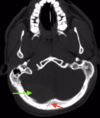

A 24 year-old man is brought to the emergency department following a single midline gunshot wound to the forehead. On arrival, he is GCS 7T with bilateral sluggishly reactive pupils and localizing in the left upper extremity to noxious stimulus. His non-contrast head CT is depicted (Figure 1). This patient is most at risk for what acute complication of penetrating brain injury? Arteriovenous malformation Traumatic intracranial aneurysm Venous sinus thrombosis Traumatic arterial dissection Cavernous-carotid fistula

The correct answer is traumatic intracranial aneurysm. These lesions may develop along any artery within the pathway of the penetrating foreign body and may increase in size or rupture with significant morbidity and mortality. Although cavernous-carotid fistula and arterial dissection may occur in both blunt and penetrating trauma, **traumatic pseudoaneurysms are more concerning in penetrating trauma**. Venous sinus thrombosis may be present after venous injury, but an arterovenous malformation would be an incidental finding.